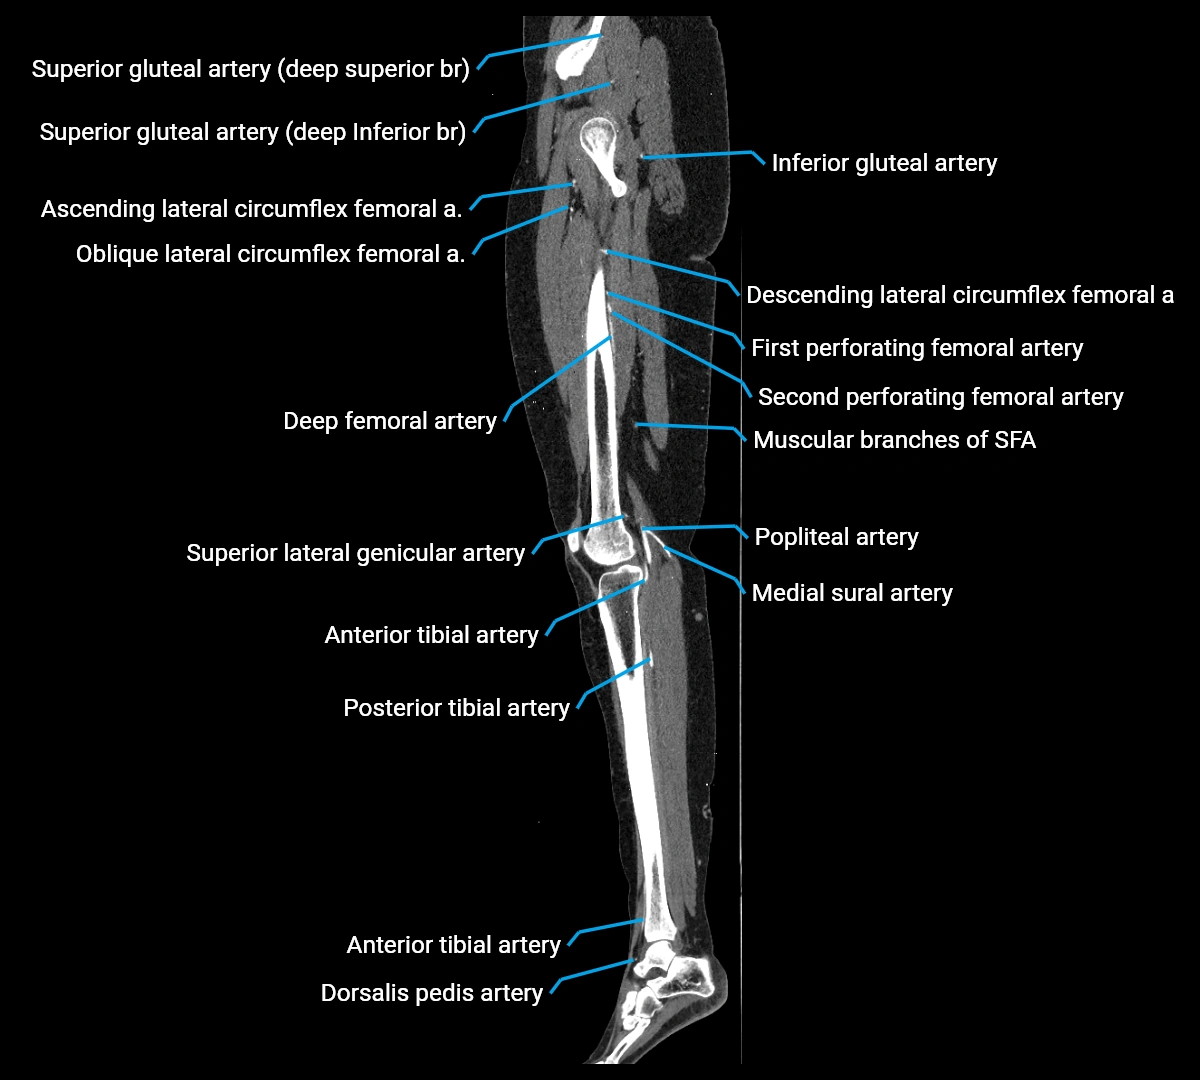

CT Appearance

Non-contrast CT:

• Appears as a tubular soft tissue structure anterior to vertebral bodies

• Calcified atherosclerotic plaques appear as hyperdense foci along the wall

• Useful for screening abdominal aortic aneurysm (AAA) size and mural calcification

Contrast-enhanced CT (CTA):

• Gold standard for abdominal aortic imaging

• Provides excellent detail of lumen, wall, aneurysm, thrombus, and branch vessels

• Multiplanar and 3D reconstructions help in aneurysm measurement, stent graft planning, and dissection evaluation

• Detects acute rupture, traumatic injury, or occlusion with high sensitivity